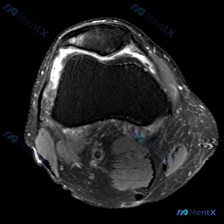

这是膝关节MRI T2序列轴位图像,读片结果整理如下:

- 髌股关节: 髌骨后方关节软骨不连续,信号增高、形态毛糙,可见片状高信号,提示软骨损伤磨损;股骨滑车关节面软骨同样信号增高、厚度不均、轮廓欠平整,对应区域可见关节积液高信号

- 关节与滑膜: 髌股关节周围及关节隐窝可见中等量关节积液,滑膜轻度增厚、信号略增高,提示存在炎症反应

- 骨髓与其他: 股骨远端和髌骨骨髓没有明显局灶水肿或骨挫伤;受限于轴位切层,交叉韧带、深部半月板无法全面评估,可见范围内软组织肌腱没有明显连续性中断